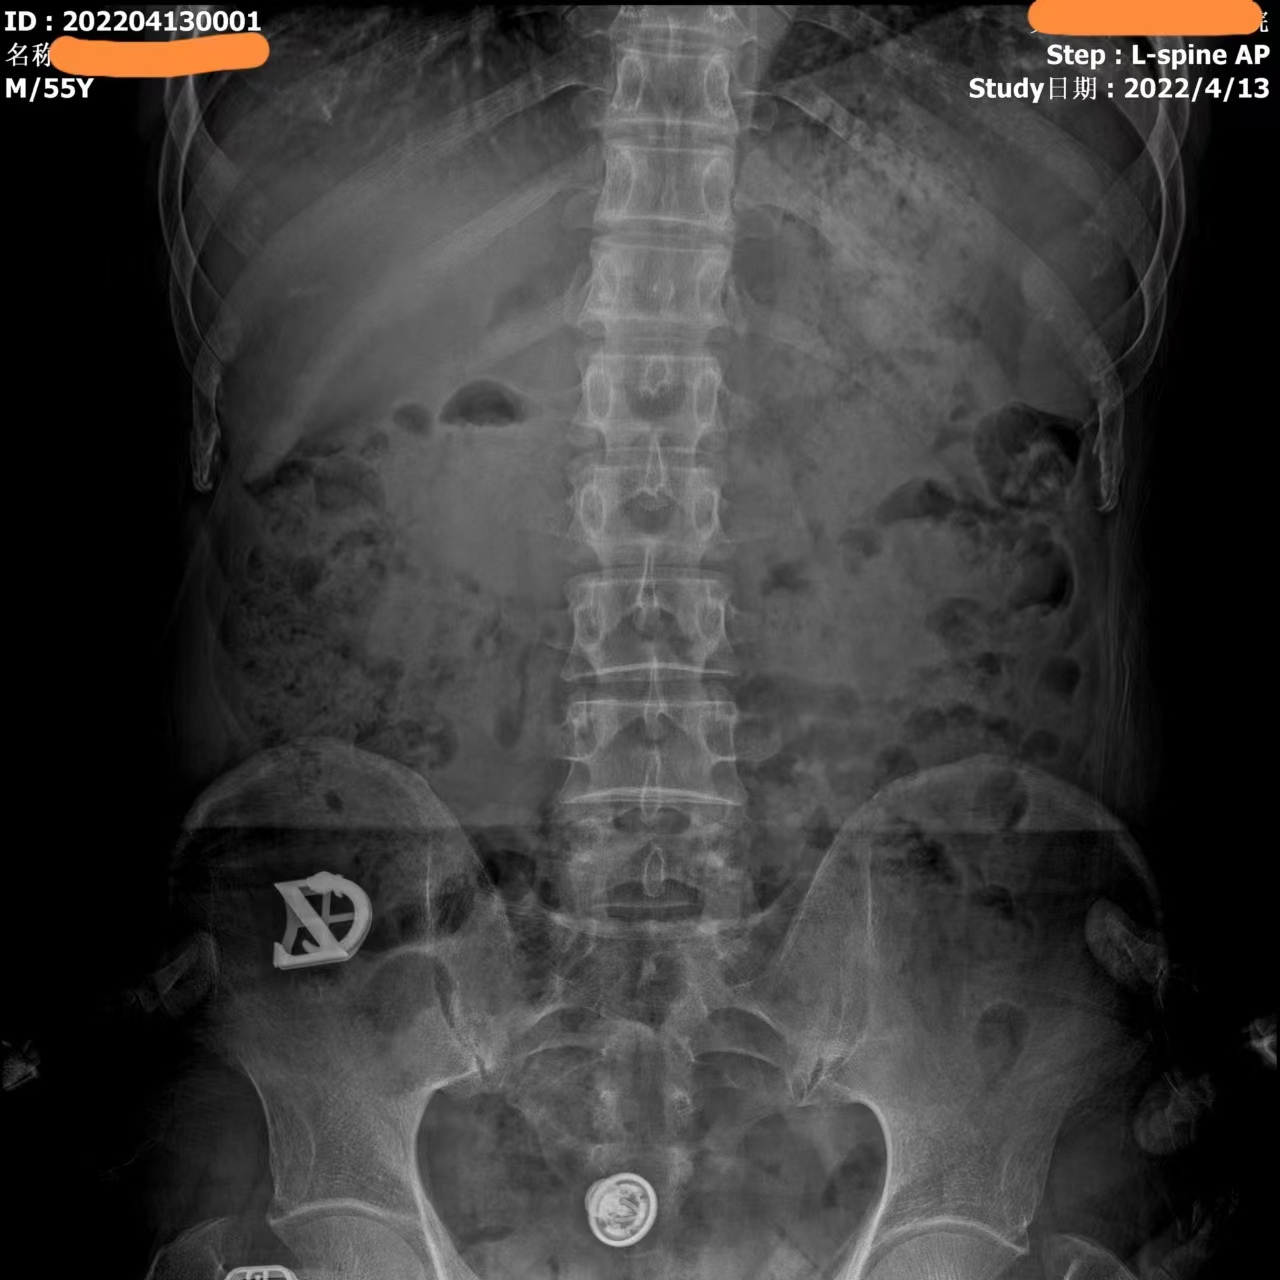

Видео с этого устройства выглядит следующим образом: